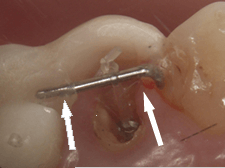

症例.6 傾いた歯をまっすぐ起こす

| 赤矢印の方向に咬む力が加わると 白矢印部分の骨が吸収していきます。 |

装置を入れました。 比較的小さな装置です。 |